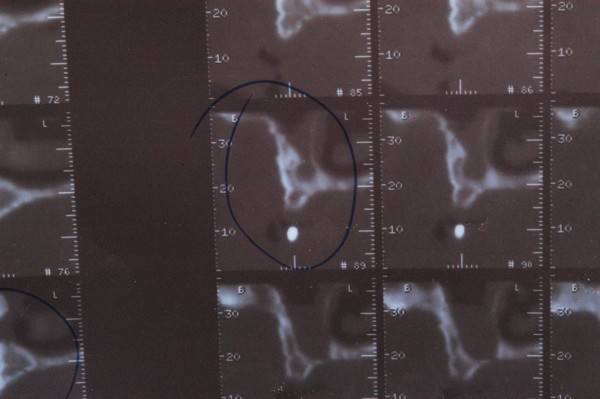

ABSTRACT La literatura oclusal se ha encargado de describir distintas funciones de la misma a través de los tiempos. El presente caso se realiza en forma de sobredentadura (over denture) debido a que la carencia de reborde óseo en el sector anterior verificado tanto clínicamente como mediante telerradiografía , impedía llevar a cabo una prótesis fija , por lo que se optó por un sistema de pilares ceramizados y paralelizados mediante el sistema SIRIUS, sobre seis implantes, y la conexión a una estructura de metal cerámica FIJA AMOVIBLE, mediante coronas telescópicas galvanizadas, otorgando al sistema la rehabilitación mediante una PIA(Prótesis Implanto Asistida con reposición ósea y gingival mediante porcelana rosa.) MATERIAL Y MÉTODOS: IMPLANTES:KLOCKNER SK-T.T.S. MONTAJE Y REGISTROS: ARCO FACIAL ESTÁTICO Y ARTICULADOR PRIMARIA: Abuttmets Ceramizados (I.P.S. D.SIGN IVOCLAR) SECUNDARIA: Cofias Galvanoformadas (AURO GALVAN CROWN WIELAND) TERCIARIA: Férula de Porcelana sobre Metal (I.P.S. D. SIGN IVOCLAR) CEMENTADO INTERFASE: NIMETIC CEM-ESPE DESARROLLO Se presenta el paciente a la consulta requiriendo la resolución de su maxilar inferior, el que se restaura mediante una férula de metal porcelana , en la que se preparan los lineamientos oclusales ideales (Spee-Wilson-Cuatro Niveles-etc) a fin de tener un sustrato de trabajo correcto, para la confección del maxilar superior, que porta una Prótesis Total convencional. Se estudia mediante Panorámica, Dentascan y Montaje en articulador semi ajustable. Se instalan seis implantes Klockner con Técnica Semisumergida pensados para una Carga diferida a tres meses después de la implantación Se realiza el arrastre de los Transfer mediante cubeta individualizada y fenestrada. Se confeccionan los abuttmentes correspondientes y se llevan a boca mediante una férula de posicionamiento realizada en Acrílico Duralay, el que por sus condiciones de carencia de cambios volumétricos verifican el correcto ajuste de los mismos Se ceramizan los abuttments y se paralelizan mediante el sistema SIRIUS, llevándolos a boca y chequeando su instalación Se confecciona una Prótesis Total Provisional que llevará el paciente durante el período de Osteointegración Se procede a la confección en laboratorio de las cofias galvánicas Sobre un nuevo modelo mayor se confecciona la férula de metal que uniremos en boca a las cofias galvanizadas mediante un cemento especial, una vez confeccionada la porcelana. Se prueba en boca la férula metálica, verificando su holgura que será ocupada por el cemento antedicho, y se comienza con el montaje de la cerámica y la verificación de los patrones oclusales de la misma. Se instala el todo haciendo morder al paciente con el medio cementante instalado. FIGURA 40 FIGURA 41 FIGURA 42 CONCLUSIONES La función de «GUIA CANINA», como esquema mas propicio para cumplir con los deseos de «autoprotección » de un SEG, rehabilitado o no, no se cumple al 100 % en casos como el presentado. La razones por las cuales el uso de la misma en lo que se da en denominar OCLUSIÓN MUTUAMENTE PROTEGIDA consiste en tres factores que detallo a continuación: A. En una función desoclusiva realizada por las piezas anteriores, como por ejemplo el canino, el BRAZO DE RESISTENCIA generado en la palanca desoclusiva, es por lo menos igual al brazo de potencia desarrollado, argumento de gran peso para hablar de la Desoclusión Canina como esquema de elección- B. La inclinación de los rebordes marginales del canino superior, esta dentro de los 70º, a diferencia de la tabla oclusal posterior que puede variar entre los 20 y 40 º. C. El estimulo que generan los dientes anteriores se dirige por via aferente al SNC, exitando por vía eferente, fundamentalmente al músculo temporal en sus fibras anteriores o VERTICALES…fibras de mucha menos capacidad de fuerza, que si la acción la ejercieran las fibras de la cincha PTERIGO MASETERINA, que serían exitadas en el caso de una Función de Grupo. EN EL CASO PRESENTADO LAS DOS PRIMERAS RAZONES TIENEN VIGENCIA. Sin embargo la última de ellas , al no tener los Implantes terminaciones nerviosas como las que posee el periodonto , los estímulos que llegan al SNC no se cumplen, y por lo tanto no existe la respuesta que por conducción eferente estimularía al músculo temporal a su acción. De la misma manera, el hecho que estos Implantes estén ferulizados , trasmite fuerzas laterales también a los posteriores, y no solo a los que actúan como caninos. El beneficio de las dos primeras razones de uso de una Función Canina en un caso como este, obedece a que de por si las mismas minimizan la acción direccional de las fuerzas, las que sin embargo son compartidas por las piezas posteriores tanto del LT como del LnT. En este compartir de la función, me resulta conveniente denominar a este esquema: FUNCIÓN DE GRUPO POSTERIOR DE ACCIÓN CANINA. ———————————————————————————————————- PIE DE FOTOS: 37: CASO TERMINADO